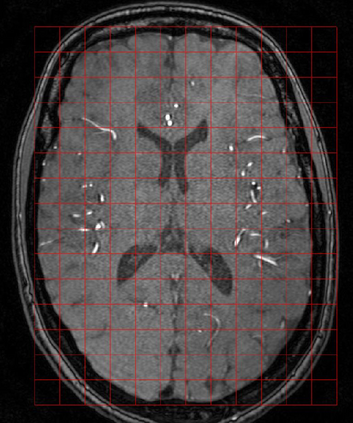

The use of deep learning techniques for 3D brain vessel image segmentation has not been as widespread as for the segmentation of other organs and tissues. This can be explained by two factors. First, deep learning techniques tend to show poor performances at the segmentation of relatively small objects compared to the size of the full image. Second, due to the complexity of vascular trees and the small size of vessels, it is challenging to obtain the amount of annotated training data typically needed by deep learning methods. To address these problems, we propose a novel annotation-efficient deep learning vessel segmentation framework. The framework avoids pixel-wise annotations, only requiring patch-level labels to discriminate between vessel and non-vessel 2D patches in the training set, in a setup similar to the CAPTCHAs used to differentiate humans from bots in web applications. The user-provided annotations are used for two tasks: 1) to automatically generate pixel-wise labels for vessels and background in each patch, which are used to train a segmentation network, and 2) to train a classifier network. The classifier network allows to generate additional weak patch labels, further reducing the annotation burden, and it acts as a noise filter for poor quality images. We use this framework for the segmentation of the cerebrovascular tree in Time-of-Flight angiography (TOF) and Susceptibility-Weighted Images (SWI). The results show that the framework achieves state-of-the-art accuracy, while reducing the annotation time by up to 80% with respect to learning-based segmentation methods using pixel-wise labels for training